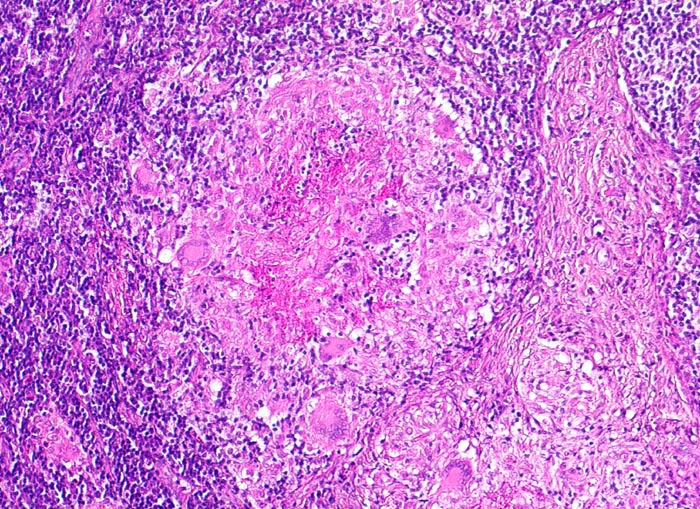

• Lymphknoten mit ausgedehnten konfluierenden eosinophilen Nekrosezonen und nur wenig erhaltenem Lymphknotengewebe (blau).

• In den grösseren Nekrosearealen sind Kerntrümmer von neutrophilen Granulozyten erkennbar.

• Demarkierung der Nekroseareale durch schlanke Epitheloidzellen, Riesenzellen vom Langhanstyp mit hufeisenförmig angeordneten Kernen und Lymphozyten.